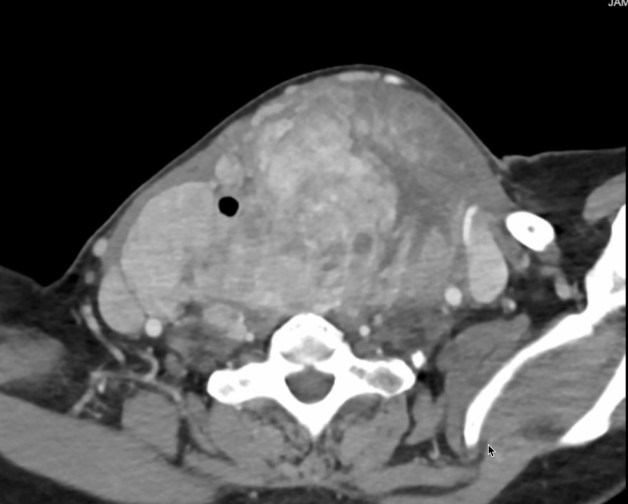

Giving Hope Through Jaw Reconstruction: Treating Ameloblastoma in Kenya

Ameloblastomas are benign but locally aggressive tumors that most often arise in the mandible (lower jaw). While they grow slowly, patients in Kenya frequently present with very large masses by the time they come for treatment — far larger than any I encountered during my surgical training in the United States. Once these tumors reach…